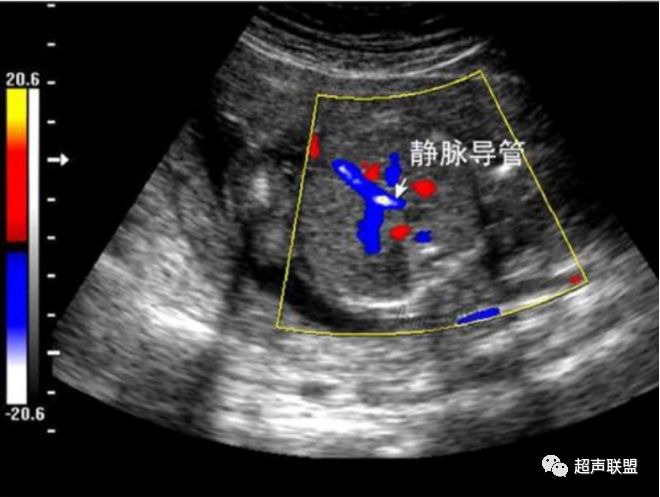

图4 大脑中动脉血流阻力减低

图5 胎儿宫内正常静脉导管

图6 胎儿宫内缺氧时静脉导管a波反向